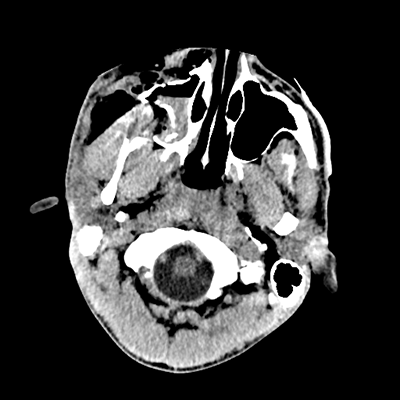

Initial vitals are notable for BP 111/67, HR 119, SpO2 100%, T 37.8C. She undergoes a whole-body CT scan. Trauma surgery also evaluates her. She has a zygomaticomaxillary complex fracture, comminuted fracture of her humerus, and fractures of ribs 2-6. Her non-contrast head CT is shown below. Plastic surgery evaluates her and recommends non-emergent operative repair of her facial fracture.

The patient has sustained multicompartmental hemorrhages—small amounts in the parenchymal, subarachnoid (mainly right frontal), subdural (right frontal, anterior temporal in particular), and intraventricular (layering in the right occipital horn) spaces. It’s a more subtle finding, but you can also see that the right hemispheric convexity has less sulcation, suggestive of cerebral edema on that side. There’s the right frontal contusion with hemorrhage there. There are also two small IPHs, in the right thalamus and left internal capsule. What do these represent? Likely diffuse axonal injury (DAI).